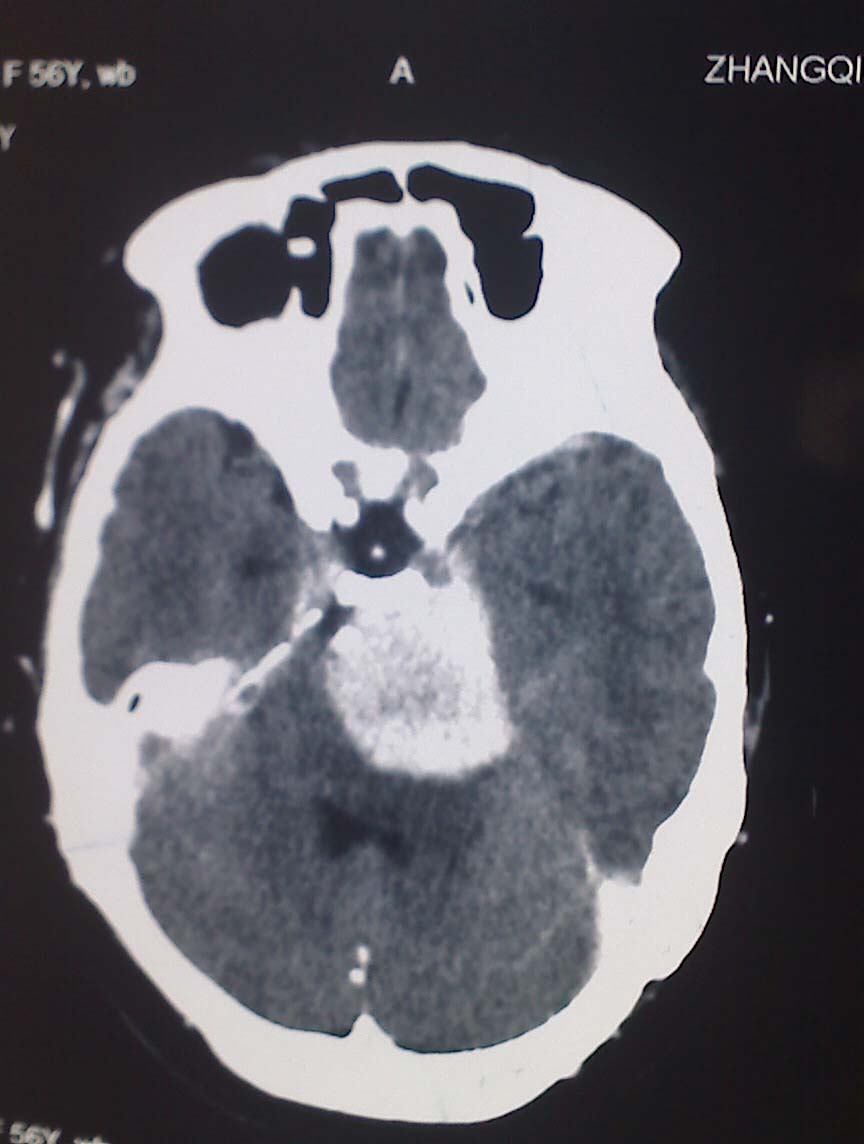

女性,56岁,查体所见,请会诊

平扫为较高密度,增强后病灶明显强化,边界清楚水肿不明显.考虑脑膜瘤.

左岩骨尖区脑膜瘤

从病变位置和强化表现看倾向脑膜瘤,但其跨越中后颅窝,也要结合临床,不能忽略三叉神经瘤,不过后者囊变较多。此病例的不足是无骨窗对照,脑膜瘤比较容易出现临近骨骼的异常。

左岩骨尖区占位病变,平扫呈高密度,病变跨中后颅窝生长,岩骨可见骨质吸收,周围未见明显水肿,增强扫描病灶明显强化。考虑左岩骨尖区脑膜瘤。

此片最大的缺憾是没骨窗,钙化及颅骨的改变不好看